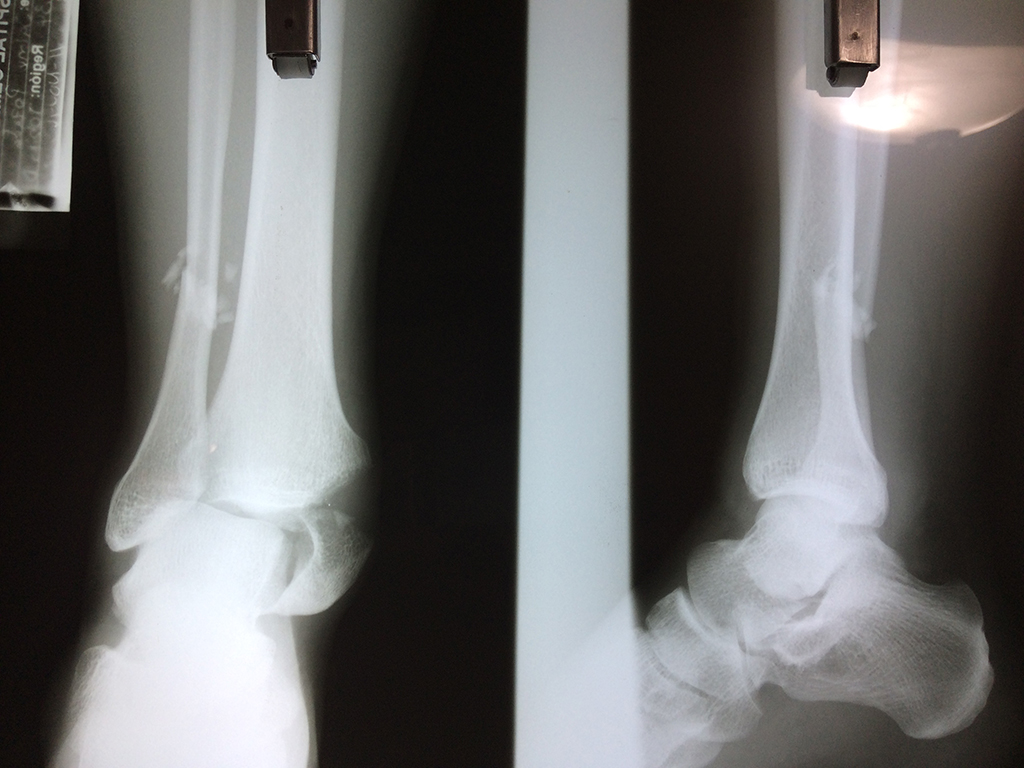

Una fractura de tobillo es la rotura de uno o más de los huesos del tobillo. Estas fracturas pueden ser:

- Parciales (el hueso está sólo parcialmente fisurado, no del todo).

- Completas (el hueso está perforado y está en 2 partes).

- Producirse en uno o ambos lados del tobillo.

- Los extremos de los huesos están desalineados entre sí (desplazados).

- La fractura se extiende hasta la articulación del tobillo (fractura intra-articular).